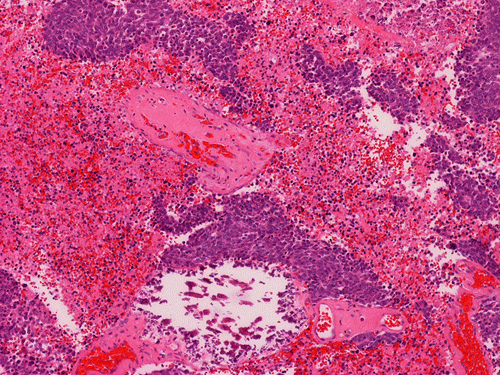

| G. | H. | I. | J. |

On permanent sections, there is extensive necrosis (Panel G) and there are numerous small islands of pyknotic or apototic nuclei (Panel H). In non-necrotic areas, the nuclei are large and pleomorphic. There are numerous mitotic figures (Panel I). Nuclear wrapping (Arrow in Panel J) is readily seen. The tumor is focally positive for synaptophysin, neurofilament proteins, glial fibrillary acidic protein, and diffusely positive for antibody BAF47.

Large cell (anaplastic) medulloblastoma is characterized by large, vesicular nuclei that are 5 times or more the size of a red blood cell. Marked variation in nuclear size and contour, and multinucleated, bizarre giant cells are other features. In particular, nuclear hugging or nuclear wrapping which refers one nucleus being surrounded by other nuclei as illustrated in this cases is a classic features of large cell medulloblastoma. In contrast to the classic type of medulloblastoma, the nucleoli are prominent, necrosis is prominent and extensive, extensive apoptotic or pyknotic cells are common. Large cell medulloblastomas have numerous mitotic figures that far exceed what would be expected in a classic medulloblastoma. Attempts has been made for a grading system of anaplstic changes in medulloblastoma 1 but the value of this system still has to stand the test of time 2, 3.